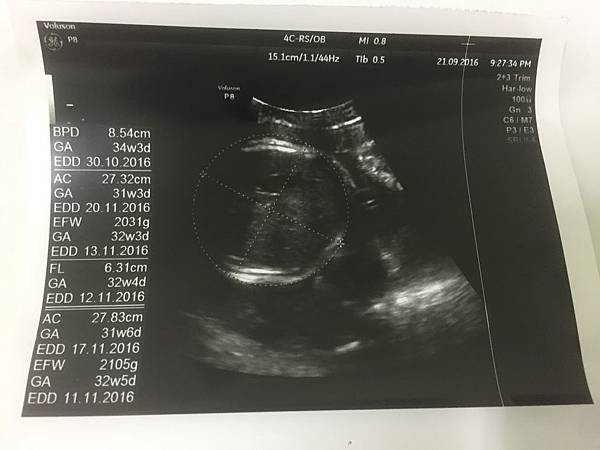

34.5週的葉黃素體重來到2000公克

兩個禮拜增加200公克~怎麼覺得有點少!

醫生也說寶寶還是有點輕,頭圍是正常週數

但身體、四肢少2~3週

(現在產檢的超音波照每次都是這個哈哈)